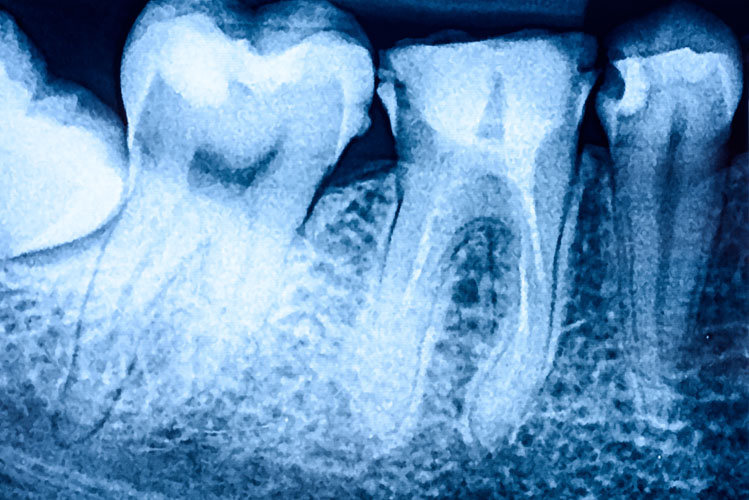

Most people dread seeing the dentist on a good day, let alone on an emergency basis. Unfortunately, it is common for patients to develop infections, or fractures around the teeth which requires us to extract a tooth. Traditionally, the tooth would be removed, and the patient left biting on a gauze pack. This technique was effective, but the resulting bone loss can create future dilemmas down the road. Fortunately today, we can help prevent bone loss following extractions.

Routinely, when we extract a tooth in our office, the patient is offered Socket Preservation. This is a fancy term for bone grafting. When a tooth is lost, we can expect 40-60% of the surrounding bone to atrophy within the first 2 years, and 1-2% each year thereafter. The bone grafting procedure helps to eliminate the significant initial bone loss, "preserving" the integrity of the extraction site. This becomes important when it comes time to restore the site with a dental implant, bridge, or denture.

When a dental implant is planned, the area must have not only enough bone height and width to hold it, it must be quality dense bone. Bone grafting helps maximize those three features. Even if a dental implant is not planned, maintaining the bone below a bridge of denture is paramount to help support the dental prosthesis, and to achieve maximum aesthetics.